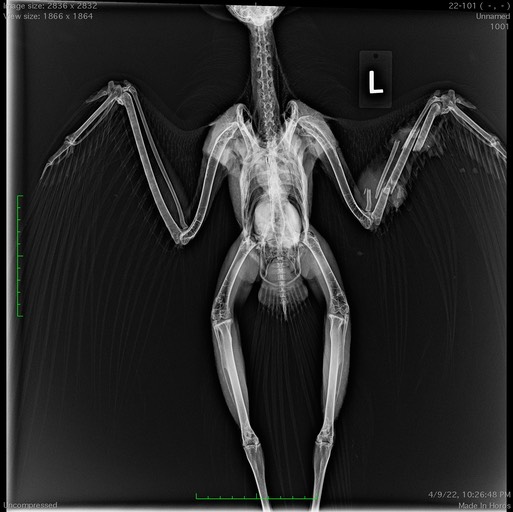

It seems like every week we see another gunshot bird. This week was no exception. An immature Bald Eagle was found near Yakima. It has an ulna fracture caused by a projectile which can be seen in the radiograph below.

The eagle’s wing has been immobilized. The hope is that the intact radius will act as a splint for the broken bone. The eagle is not a very happy patient!